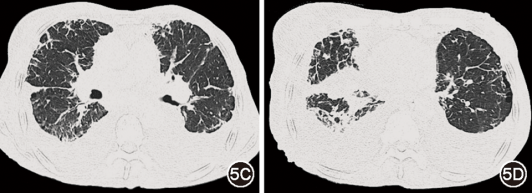

图5  治疗后(2025年10月23日)胸部CT:双肺间质病变、胸腔积液较治疗前轻度加重

后续患者于血液科治疗,目前已完成8程Dara-VenD治疗:达雷妥尤单抗1 800 mg/次、1次/周;维奈克拉200 mg/次(因白细胞低减量)、1次/d;地塞米松20 mg/次、1次/周。气短好转,右乳及下肢水肿部分减轻,可耐受家务活动,监测指氧饱和度94%左右。治疗9个月后复查血游离轻链κ下降至9.9 mg/L,血液学完全缓解,心脏病情稳定,CT示双肺间质病变、胸腔积液轻度加重(图5),考虑和已沉积的淀粉样物质清除困难有关,但病情进展速度减缓。

患者根据血液科医师制定的方案进行全身治疗,尽管已达血液学缓解,其肺部与胸膜病变却持续进展。肺间质淀粉样变出现影像学改善极为少见,可能与已沉积的淀粉样物质难以自行清除,并持续导致器官损伤有关[14, 15]。然而,目前暂无药物获批于清除沉积物,治疗仍以抗浆细胞及支持治疗为主。CAEL-101为靶向淀粉原纤维单抗,可清除器官中的纤维聚集体,已在Ⅰ/Ⅱ期试验中验证疗效,有望为改善预后带来突破[15]。